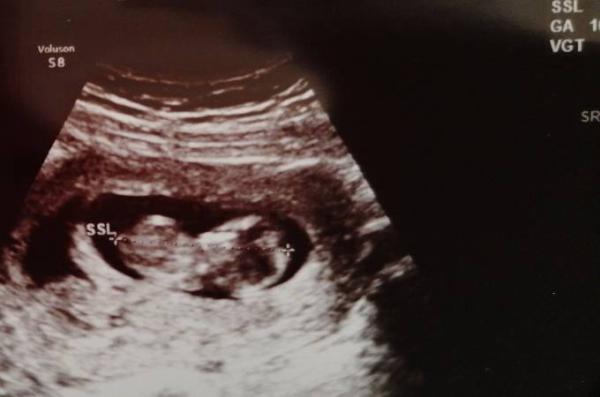

Hallo :) ich komm gerade vom 2 Ultraschall. Ist soweit alles super. Bin vordatiert auf den 3.6. 20. Sie meinte Geschlecht is schwer zu sagen aber sie denkt 60% junge. Passt so garnet zu meinem eigentlichen Gefühl.

Naja abwarten  ist ja auch noch zimmlich früh.

Da ist noch das Foto vom Zipfel. Kann euch leider Keinen Pfeil hin machen. Is der po von unten.